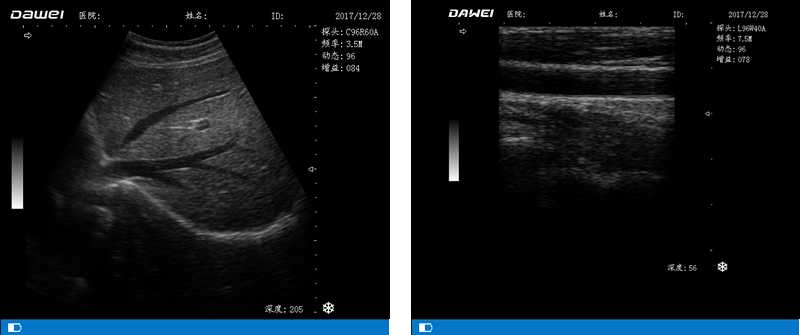

DW-500

筆記本全數(shù)字超聲診斷儀

高陣元 高清晰度 多功能

多倍率顯示 病變?cè)\斷更準(zhǔn)確